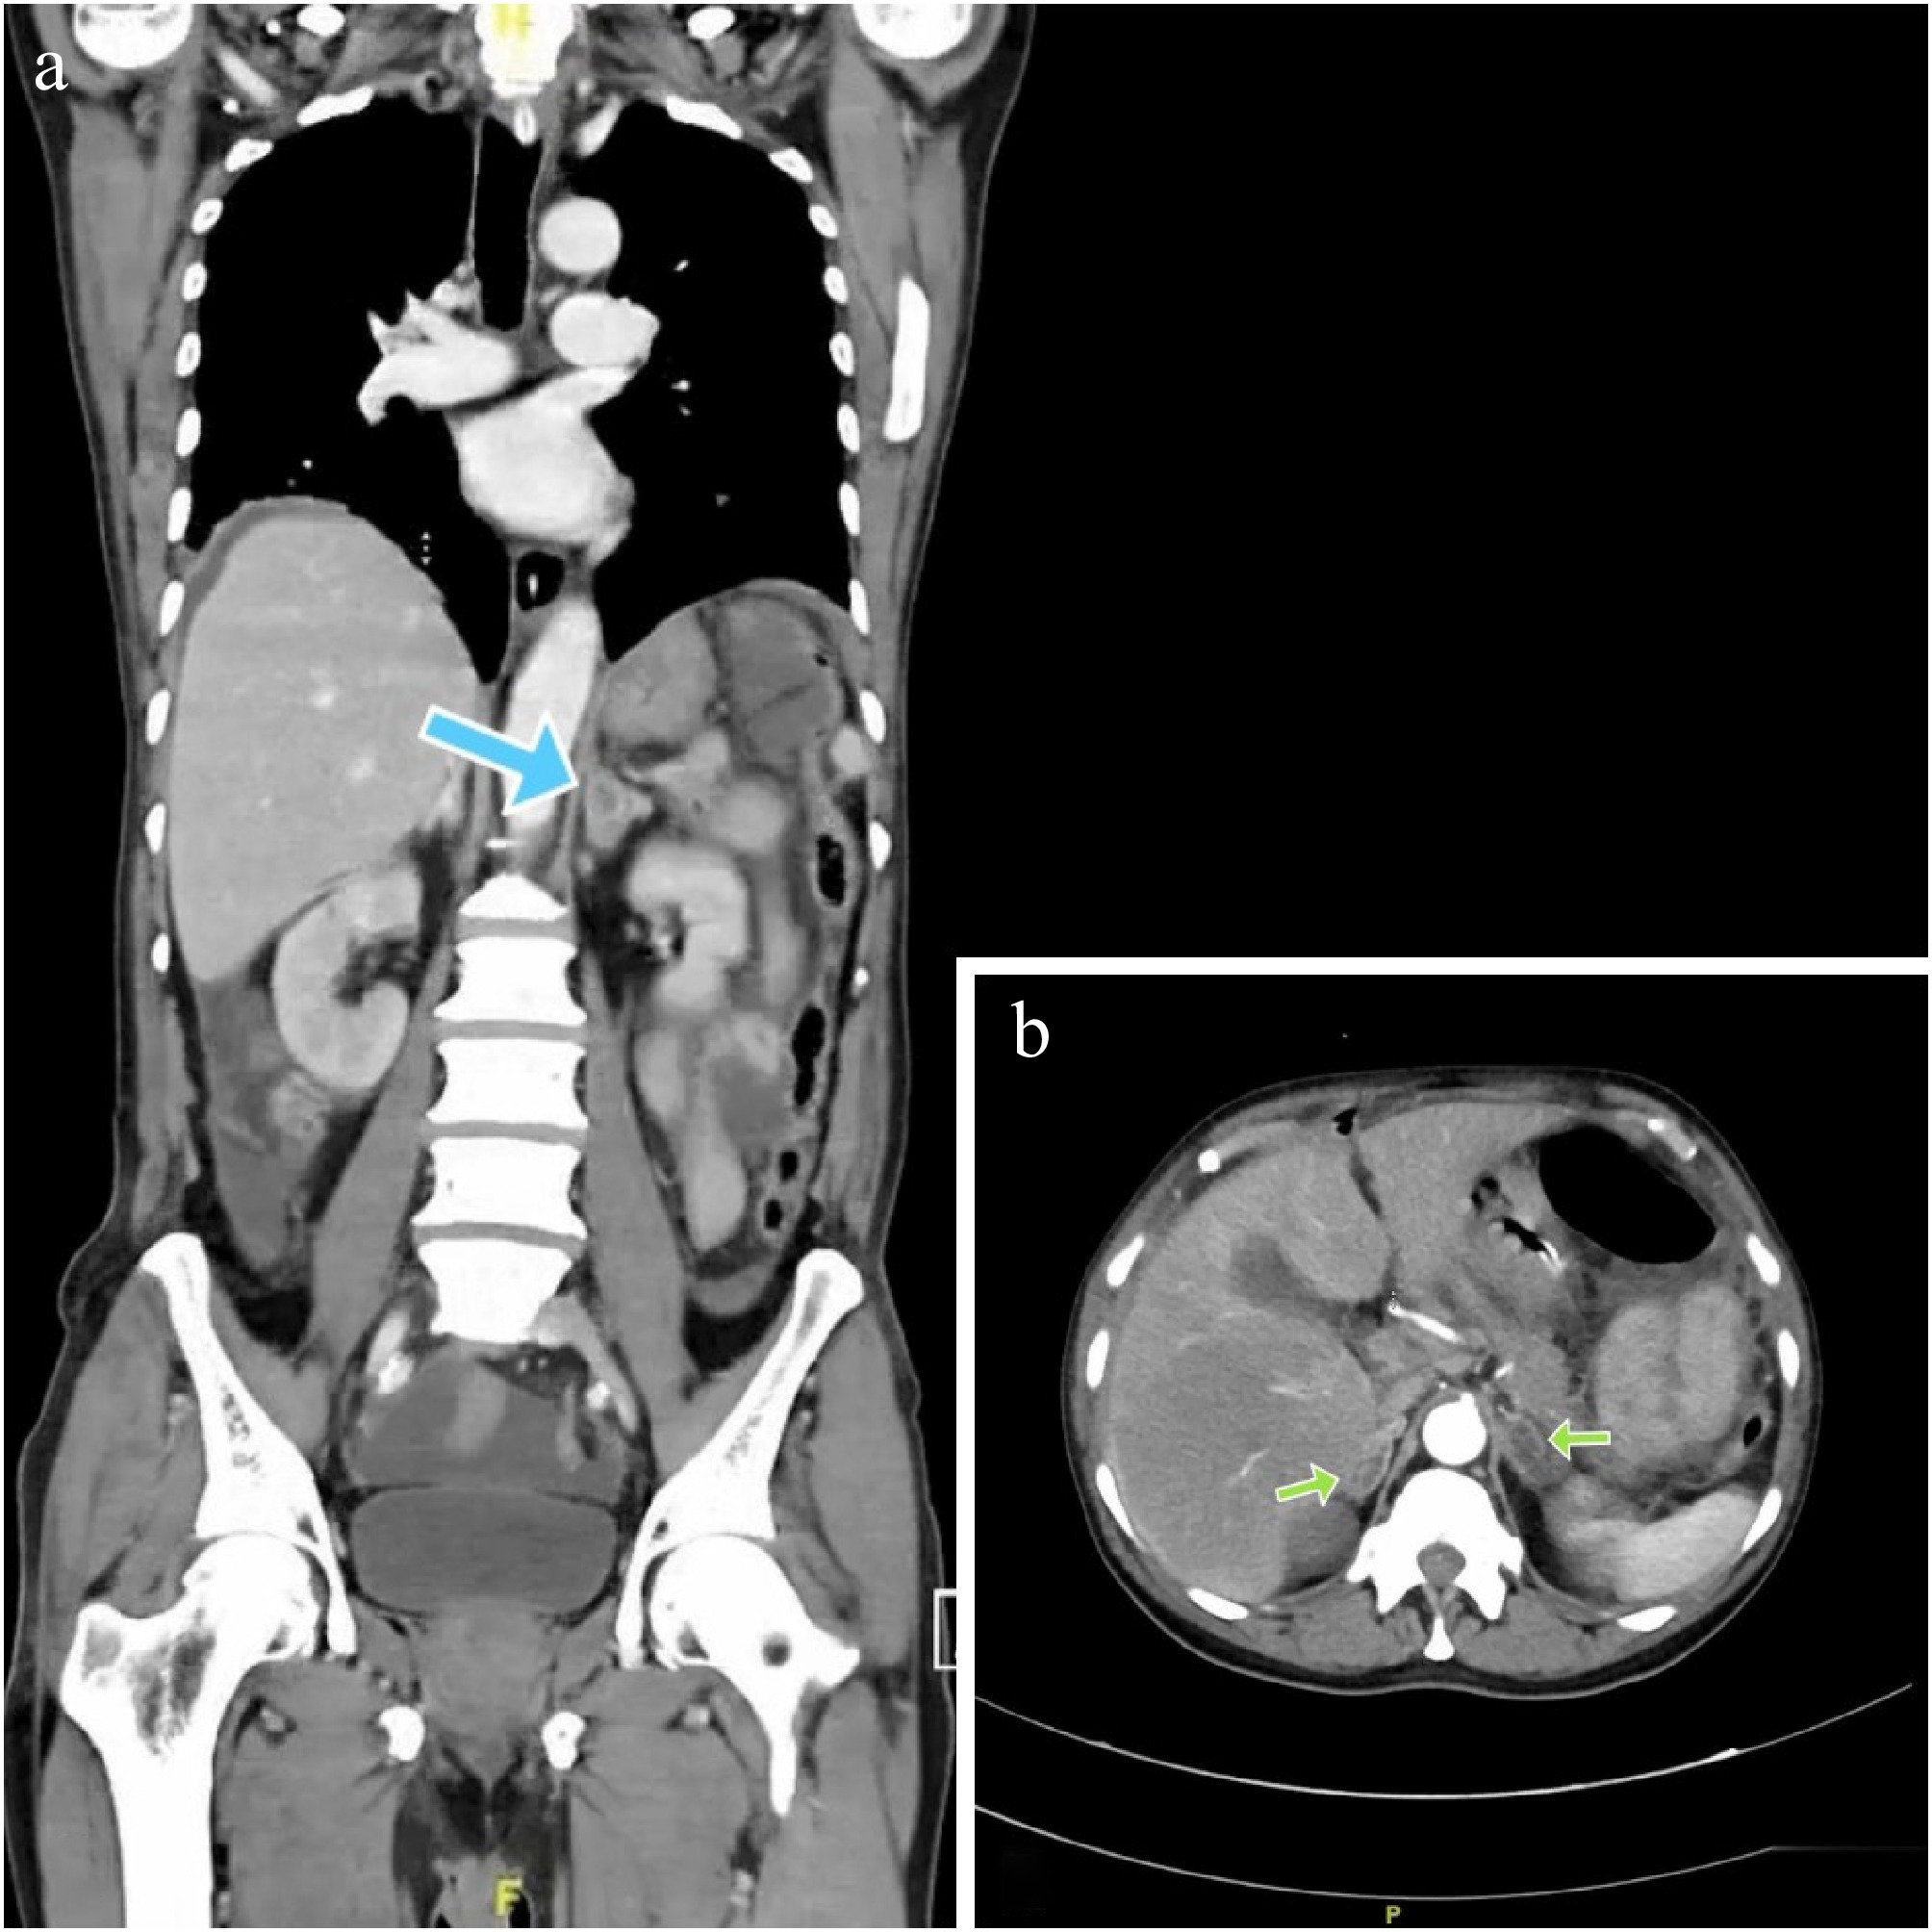

There were ill-defined hypodense areas seen in bilateral adrenals, likely metastatic deposits (Fig. 2a & b).

Figure 2.

(a) Blue arrow showing a hypodense lesion in the left supra-renal gland. (b) Green arrows showing bilateral hypodense adrenal lesions (Hounsfield units: min- 20, max- 104, avg- 38).